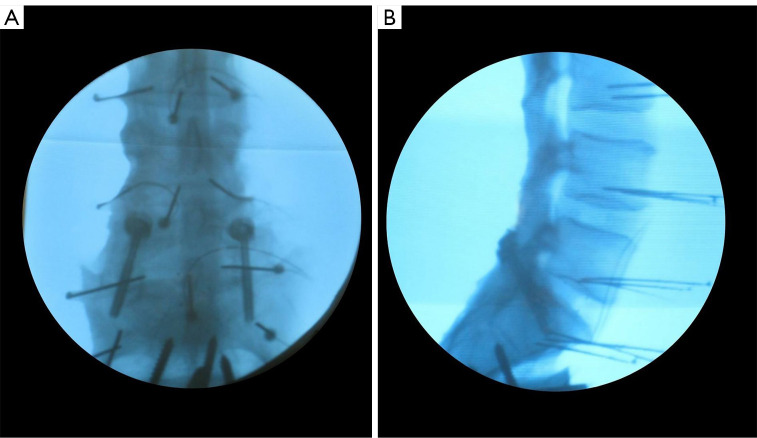

Methods: Cadaveric biomechanical testing was conducted in vitro to evaluate the stability of posterior fixation using bilateral TFPS (FacetFuse®, LESSpine, Burlington, MA, USA), bilateral and unilateral PSR (PedFuse Return, LESSpine, Burlington, MA, USA) constructs measuring 5.0 mm × 40 mm. A comprehensive analysis of range of motion (ROM) and stability under various loading conditions was performed to a maximum of 7.5 Nm. The constructs were assessed for their ability to provide immediate stability at the L5-S1 disc level.

Results: Fourteen specimens were analyzed with an average age of 53.14±10.99 years and comparable bone mineral density. TFPS demonstrated a reduced ROM that was notably lower than that of unilateral PSR in all loading modes and was comparable to bilateral PSR, especially in extension and axial rotation (AR). The unilateral and bilateral PSR groups differed notably in lateral bending (LB) and AR.